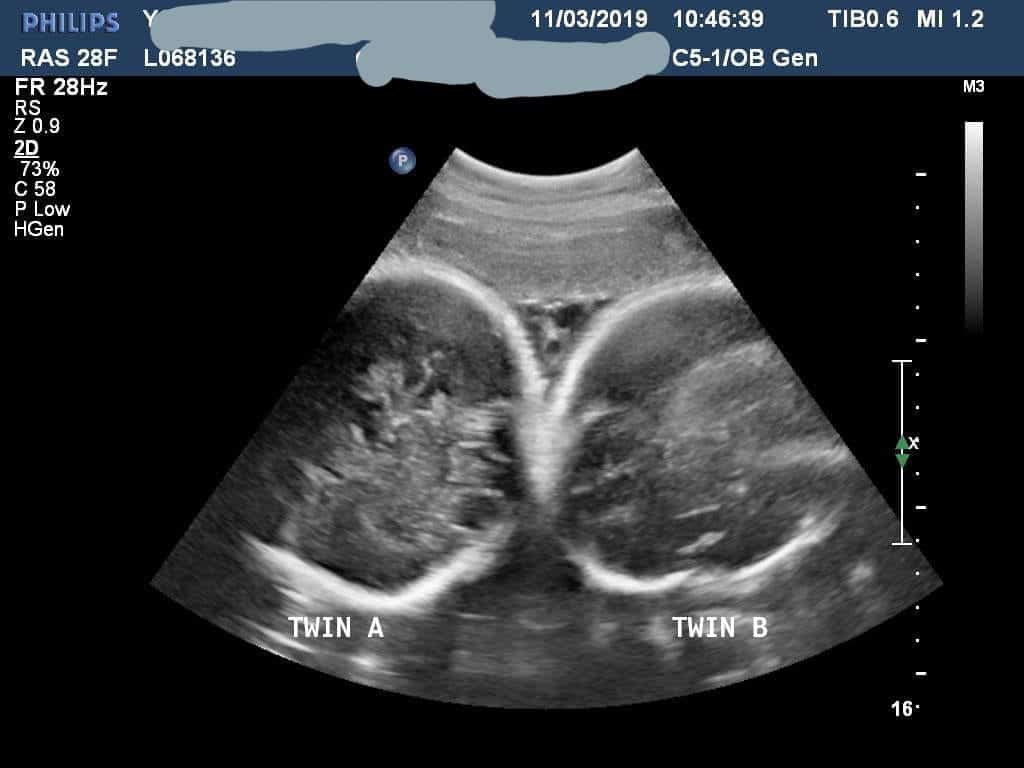

- Ultrasound Photos at 35 Weeks Pregnant With Twins

Ultrasound Photos at 35 Weeks Pregnant With Twins